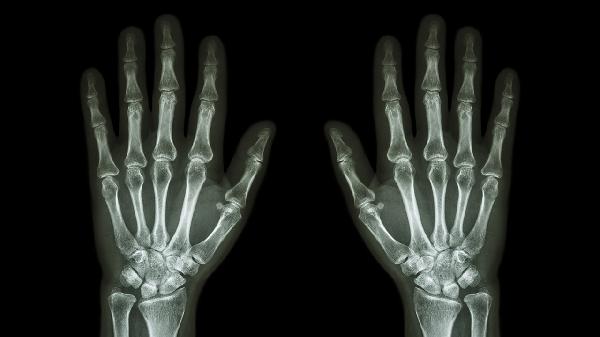

中老年人群关节软骨退化可能引发摆动痛,晨僵时间通常不超过30分钟。X线可见关节间隙狭窄。可遵医嘱使用硫酸氨基葡萄糖胶囊、塞来昔布胶囊等药物,配合关节功能锻炼。体重控制有助于减轻关节负担。